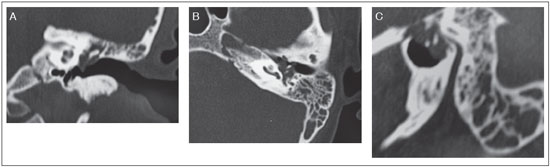

The patient consulted a colleague who raised the possibility of a tympanic paraganglioma. Computed tomography (CT) of the temporal bones revealed a material with a soft tissue density that diffusely obliterated the left mastoid cells, but with no signs of ossicular chain erosion (Figure 1). Angiography of the temporal bone showed a lobulated solid lesion with defined limits and contrast uptake within the left middle ear and the epitympanic recess.

Figure 1. Computed tomography of the temporal bones revealed a material with a soft tissue density that diffusely obliterated the left mastoid cells, but with no signs of ossicular chain erosion. A. Coronal B. Axial C. Transverse